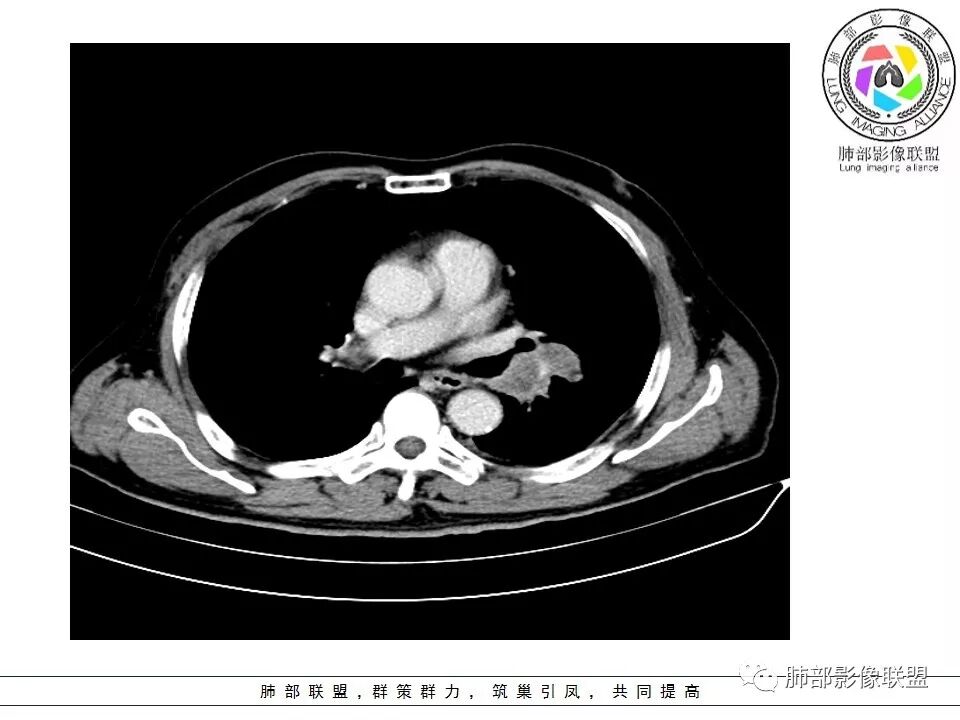

老年男性,症状轻。左肺下叶类圆形肿块,边界清楚,分叶不明显,其内无空泡征,边缘无毛刺及胸膜牵拉,远端无阻塞性肺炎。左肺门影增大。增强扫描左肺下叶肿块可疑轻度强化(无平扫对比),局部见小尾巴征。左肺门区见不规则形团块,似多个结节融合,肺动脉受压穿行于病灶中,形成冰冻肺门感觉,局部层面似见肺门区团块与左肺下叶肿块相连。综合考虑小细胞肺癌(SCLC)。

左肺门乱乱的,有血管受压表现,有支气管腔内占位表现,肺门淋巴结肿大肯定是有的;左肺下叶见一巨大包块,边缘光滑,内侧又一个切迹,考虑是病变受到了小叶间隔阻挡造成的其内部大部分不强化,但有局部一小片强化;壁不均匀环形强化,总体较薄;周围没有阻塞性肺炎,感染性病变应该是不考虑的,因为周围清楚,也没有感染的症状,还是考虑肿瘤性病变;关键是它边缘光滑,内部应该是坏死,但有强化提示坏死不彻底,这么大了,边缘恶性征象不明显,不符合腺癌,鳞癌呢也不太符合,阻塞性肺炎没有,坏死太明显了,这么大,边缘光滑,坏死明显,符合肉瘤和肉瘤样癌,不除外小细胞肺癌

南边:与肺静脉啥关系?这样追下去是不是很恶啊

尘缘:@南边 肺静脉受侵

南边:病灶分为两大块,外围囊实性大肿块,支气管关系不密切,内带多发淋巴结,侵犯支气管、肺血管,恶性没问题,按理间叶为主,或不典型的癌,这不是一个中央型的肺癌,是外朝内进展的,奇怪的是边界这么清楚光滑,一般癌肉瘤、肉瘤类多,其次才是癌,远端也没有阻塞,大方向是这样,恶性,间叶来源?或者混合,恶性程度较高,鉴别就是结核,因为结核是妖

2娘小崽大、淋巴及血行转移早、冰冻纵隔及肺门血管脂肪间隙消失

因为病灶侵袭力强,病灶易沿淋巴道、间质及心血管间隙等结构侵犯并密切挤压上述结构,常常能够观察到脂肪间隙消失。易于出现冰冻纵隔。原发灶与肺门转移灶可形成哑铃状外观,甚至转移灶体积大于周围原发灶,有人称之为“娘小崽大”。早期病灶有时很小甚或隐匿,仅能看到转移灶,或转移淋巴结与原发灶融合分界不清。病变向肺门延续的串珠样淋巴结转移也是SCLC的典型特点。

血管包埋征

病灶侵袭力强大,早期沿粘膜下疏松结缔组织及血管旁间隙扩散,包绕血管,血管会受压变形,因为小细胞癌破坏力弱,血管没有被破坏,所以仅仅表现为包埋浸润,但血流面光滑。

5.病灶内有血管走行,血管局部受压,但是强化考虑为乏血供,提示病灶内肺动脉并不是供血血管,只是病灶侵袭性强把血管包埋而已,为血管包埋征;血流面光滑,血管包埋符合SCLC。

6.左肺门淋巴结肿大,与病灶局部融合分界不清,呈冰冻肺门;而纵隔内未见肿大淋巴结,冰冻肺门符合SCLC,但是病灶主体那么大,纵隔内没有明显肿大淋巴结,不是很符合SCLC娘小崽大的特点。